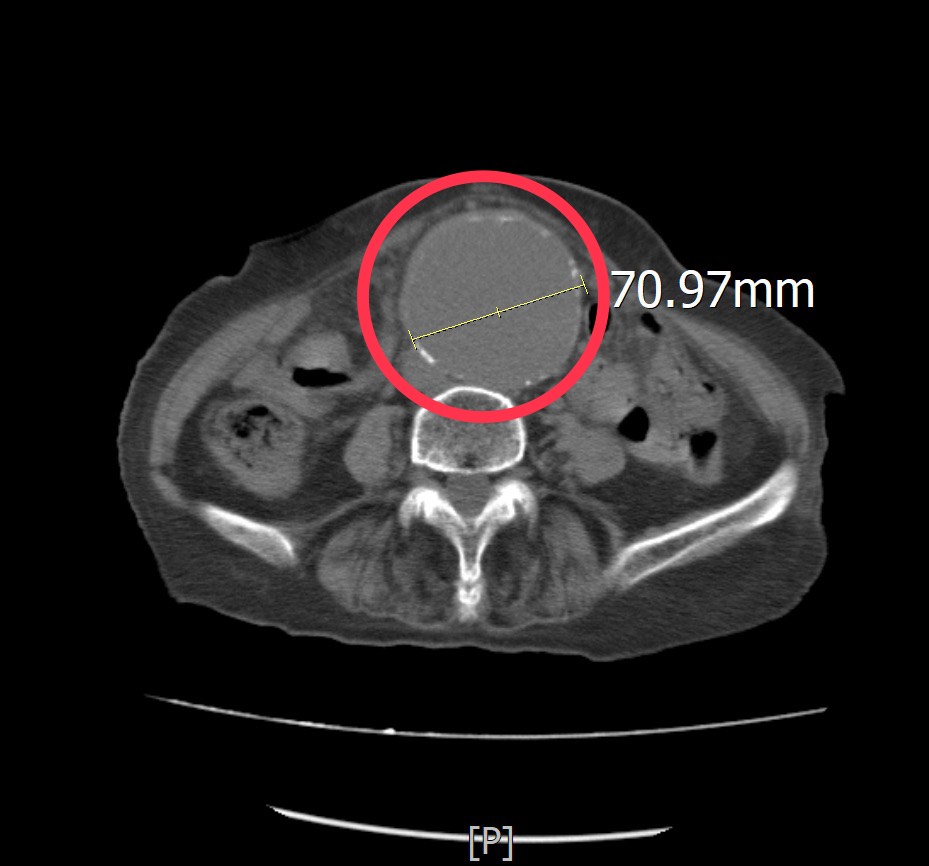

這位高齡患者由家屬陪同到急診求診時,一再強調她左側下肢痠痛及腰部不適,但並沒有明顯外傷史,其疼痛指數已達到8至10分,為了快速釐清病情,孫秀正醫師立即為病人進行床邊超音波檢查。透過即時影像檢查,發現患者的腹主動脈明顯擴張,直徑已超過7公分,高度懷疑為腹主動脈瘤,進一步安排電腦斷層檢查確認診斷,結果顯示確實為大型腹主動脈瘤。

孫秀正醫師表示,腹主動脈瘤,是腹部主動脈血管壁因退化或動脈硬化而逐漸擴張,當血管直徑持續增大,血管壁會變得脆弱,一旦發生破裂,可能在短時間內造成大量內出血,死亡率極高。當腹主動脈瘤直徑大於5至5.5公分時,破裂風險即明顯增加,而該患者的腹主動脈瘤已超過7公分,屬於極高風險狀態,因此必須儘速處理。